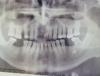

andrey_omsk Опубликовано 14 декабря, 2012 Поделиться Опубликовано 14 декабря, 2012 добрый день всем кто читает эту тему! пришел вот такой пациент. фото диагностических моделей будет позже, пока только фото панорамки. поделитесь мыслями пожалуйста, пациент согласен на все кроме имплантации. Ссылка на комментарий

andrey_omsk Опубликовано 14 декабря, 2012 Автор Поделиться Опубликовано 14 декабря, 2012 да и еще забыл, по поводу подвижности: 17,12,22,23,26,32,31,41,42- 1 степень. 37- 2 степень. 24,25- 3 степень подвижности Ссылка на комментарий

andrey_omsk Опубликовано 15 декабря, 2012 Автор Поделиться Опубликовано 15 декабря, 2012 вот что я хочу ему сделать:1. Удаление 24,25.2. Пародонтологическая подготовка3. Шинирование фронтальной группы зубов н\ч с клыка по клык глашпаном4. На н\ч бюгельный протез с опорно-удерживающими кламмерами на 37,47, и кламмера с шинирующими элементами на 35,34,33,43,44,45.5. На в\ч шинирующий бюгельный протез (съемная шина), т.к. пациент без притензий на эстетикуЖду вашей критики по поводу плана лечения. заранее спасибо Ссылка на комментарий